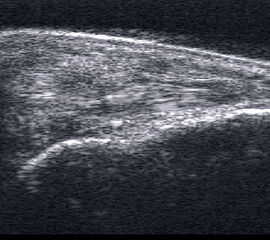

Tendopathie der Achillessehne

Lagerung: Bauchlage, ggf. Sprunggelenk mittels Rolle unterlagert.

Schnittführung: LS und TS über der Achillessehne in leichter manueller Vorspannung der Achillessehne.

Referenzstruktur: Direkt unter der Haut und der dünnen Subkutis liegt echogen und straff parallel die Achillessehne mit ihrem echogenen Peritendineum.

Befunde: Klassischerweise findet sich eine normal echogene spindelförmige Verdickung einige Zentimeter über der Insertion (Abb. 60). In der Frühphase zeigen Tendinopathien eine echoarme Verdickung. Im Verlauf finden sich zunehmend echogenere Bezirke und Inhomogenitäten, teilweise mit Einziehungen und rau erscheinendem Peritendineum. Ist die Sehne teilweise nicht mehr abgrenzbar, kann bereits ein Übergang in eine teilweise Kontinuitätsauflösung vorliegen. Ein peritendinöser Randsaum ist vor allem in frühen Phasen zu beobachten. Flüssigkeitsareale, die von der echogenen Sehne abgrenzbar sind, sprechen jedoch auch an der Achillessehne für eine Rissbildung. Auch Kalkeinschlüsse oder peritendinöse Verkalkung mit Schallschatten sowie intratendinöse Zysten werden beobachtet.